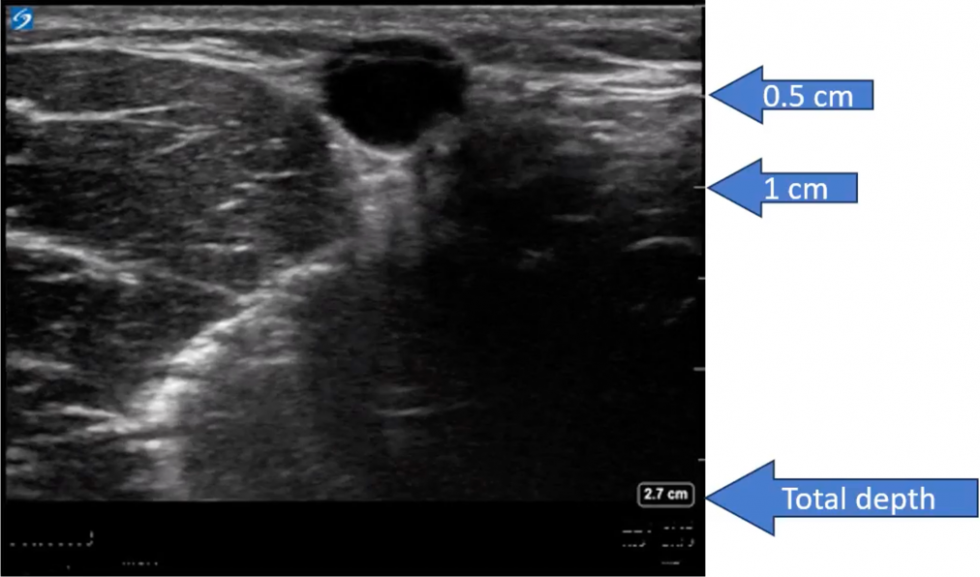

Ultrasound guide

Ultrasound guide 108 фотографий